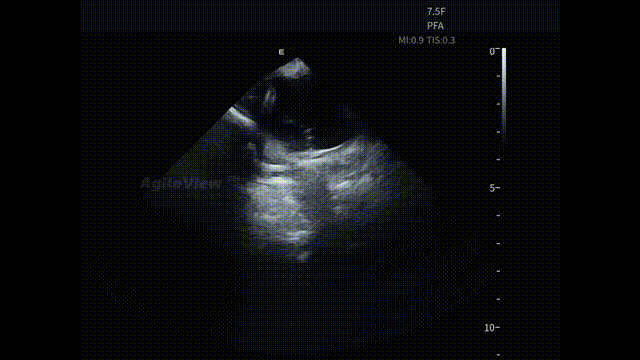

▶【消融阶段:PFA预设模式,贴靠状态可视,判断更直接】

进入消融阶段后,AgileView™ ICE 持续提供近场实时影像,动态显示消融导管与心房组织之间的空间关系与贴靠状态。在肺静脉隔离过程中,ICE 下可清晰观察到导管在左上、左下、右上及右下肺静脉口部的贴靠情况,为能量释放位置的确认提供直接影像依据。

PulseSelect™导管贴靠-LSPV

PulseSelect™导管贴靠-LIPV

PulseSelect™导管贴靠-RSPV

PulseSelect™导管贴靠-RIPV

在完成四根肺静脉口部及前庭消融后,术者使用PulseSelect™导管进行上腔静脉消融,ICE 同样用于评估导管送鞘及贴靠状态,使关键步骤始终建立在清晰可见的影像反馈之上。

PulseSelect™导管贴靠-SVC

在冷冻消融手术中,ICE 亦用于辅助评估冷冻球囊导管在肺静脉口部的封堵状态与空间位置,确保导管贴靠及消融有效性。

AFA Pro冷冻球囊封堵